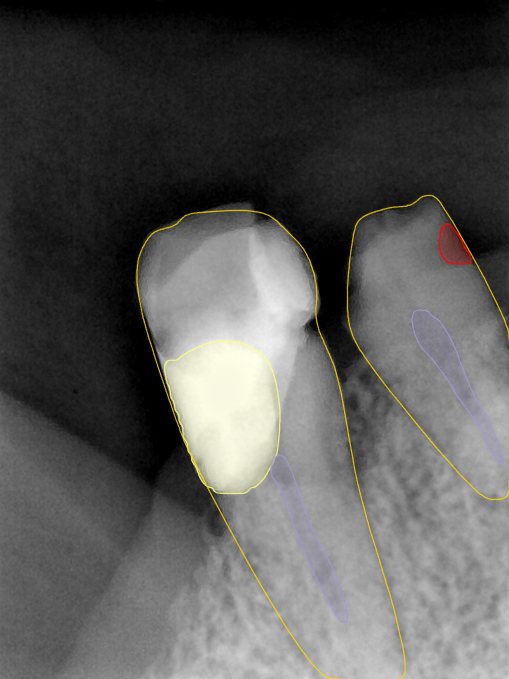

CR/DR 牙齿分割阶段记录

当前进展

- 完成了 CR/DR 牙齿相关分割训练

- 当前结果已经达到阶段预期,但仍有细节问题需要继续处理

相关测试

遇到的问题

- 训练过程中出现过 mask 下移问题

- 部分结果会出现 box 填充异常

- mask 边缘仍然有比较明显的锯齿感

第二版算法问题测试

Updated: 2026-04-13(更新日期)

| 第一版 | 第二版 | 是否解决 | |

|---|---|---|---|

![]() | ![]() ![]() 边角识别有问题 龋齿识别不全 牙髓识别不全 | ![]() | 解决 |

![]() | ![]() 边角识别有问题 识别信息有误 自查(牙冠识别不全) | ![]() | 解决 |

![]() | ![]() ![]() 边角识别有误 大范围填充识别遗漏 | ![]() | 解决 |

![]() | ![]() 识别信息不全 | ![]() | 解决 |

![]() | ![]() ![]() 边角问题 牙胶识别不全 牙冠识别不全 | ![]() | 解决 |

![]() 换图片 | ![]() | ![]() 牙冠部分稍微白了一些就识别成小范围修补,部分判断异常 | 部分解决,修复类略敏感,牙冠部分稍微白了一些就识别成小范围修补,部分判断异常。 |

![]() | ![]() ![]() 牙冠识别不全 牙髓不全 根尖炎龋齿识别有误 | ![]() | 解决 |

![]() | ![]() | ![]() | 解决 |

![]() 换图片 | ![]() | ![]() | 解决 |

![]() | ![]() 牙冠识别有误 | ![]() | 解决 |

![]() 换图片 | ![]() ![]() 边角识别有误 | ![]() 修复类敏感 | 部分解决,图像过白,导致修复类判断异常。 |

![]() 换图片 | ![]() 牙冠识别不全 | ![]() 修复类敏感 | 部分解决,图像过白,导致修复类判断异常 |

结论:修复类出现了不鲁棒的情况,后续需要加入轮廓的扩充数据进行增强。